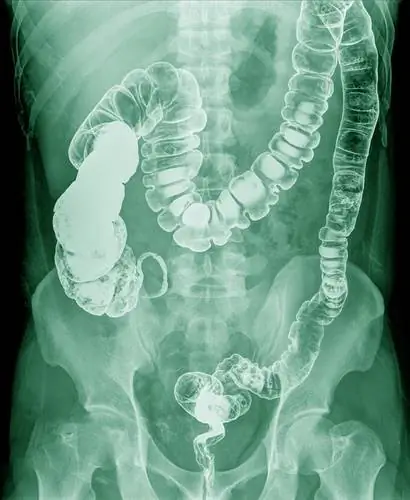

загруженный кишечник-рентген-удерживает-фекалии